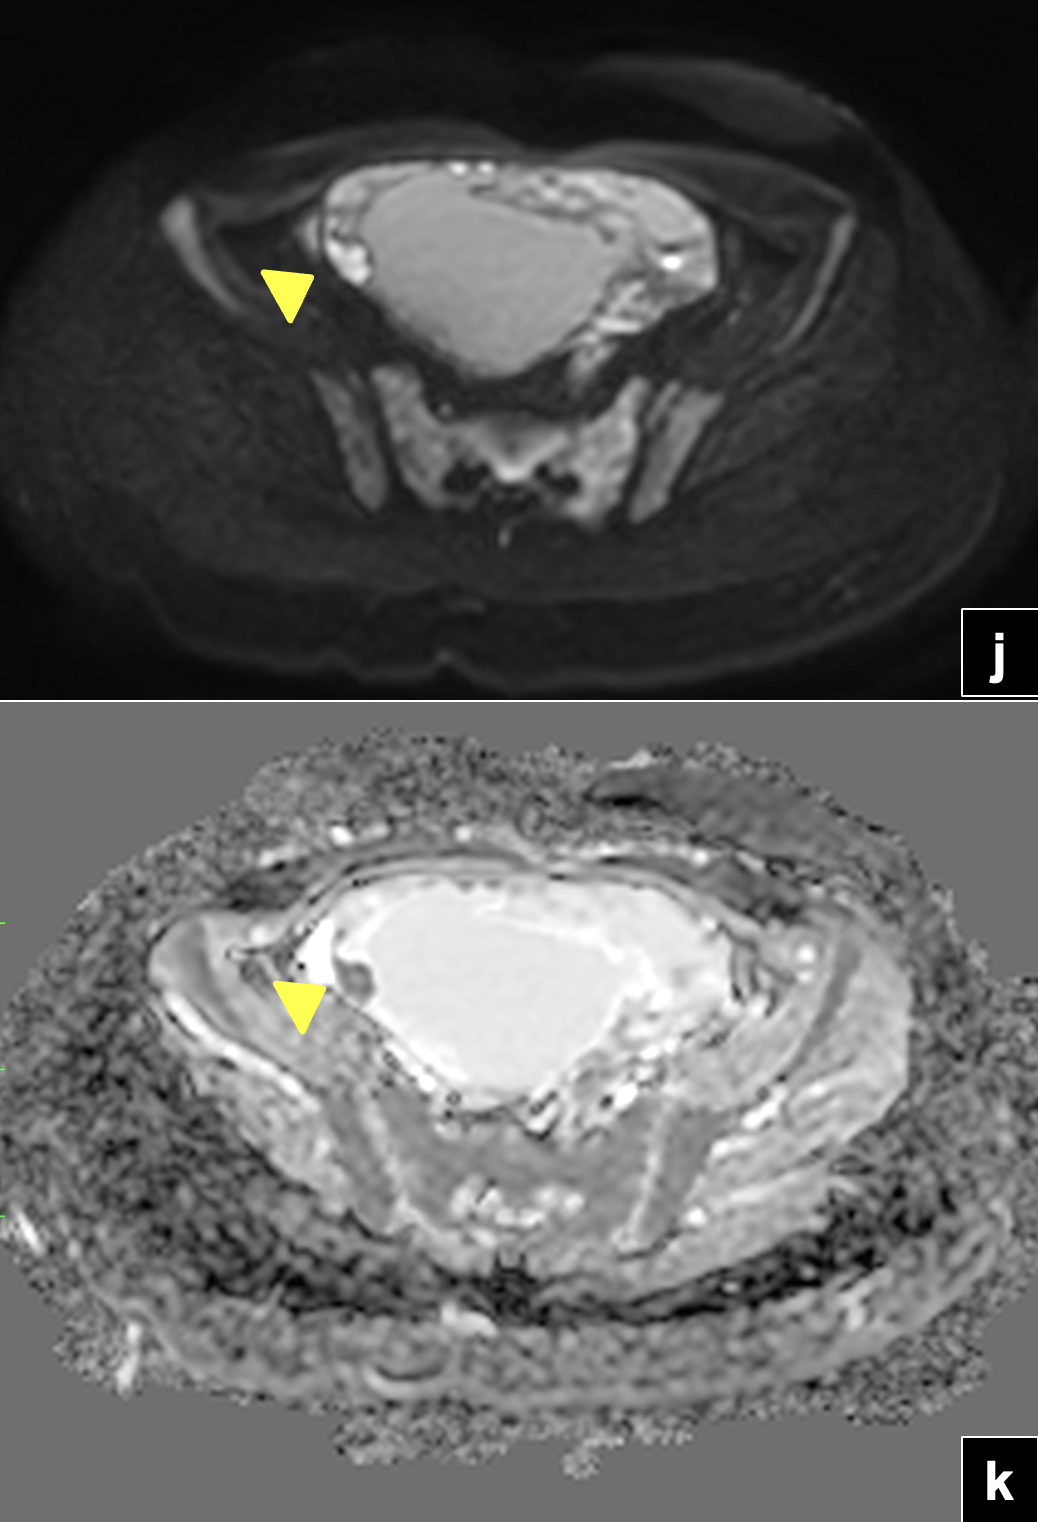

RM de abdomen y pelvis: (f) Secuencias T2 sagital. Se observa tumor solido de íleon distal (flecha) con componente quístico tabicado en hipogastrio (cabeza de flecha). Se visualiza ovario derecho de morfología conservada (asterisco). (g) Secuencia T1 FSE con Gadolinio en plano coronal. Masa quística hipogástrica con tabiques e imagen nodular periférica que realza con el uso de contraste (flecha). Efecto de masa intrabdominal visualizado por el desplazamiento hacia inferior de la pared vesical.Secuencias de pelvis axial en difusión (h,j) y mapa ADC (i,k), que demuestra restricción a la difusión de protones del componente solido del tumor de íleon en estudio y del componente sólido periférico de la masa quística hipogástrica (flecha y cabeza de flecha).